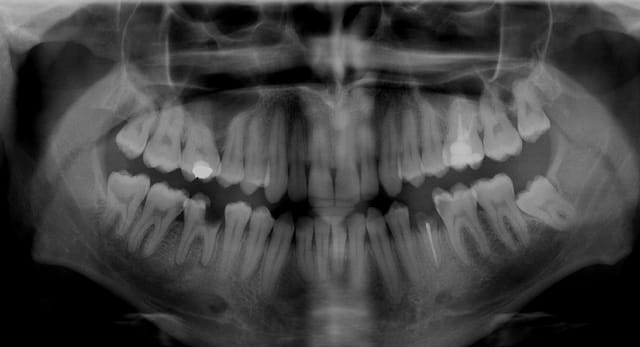

Les canaux mésiaux sont obturés, c'est dommage, mais ça ne change pas grand chose dans le cas présent. Le pire à reprendre c'est le distal car obturé à l'apex, mais c'est pas un drame non plus.

On me demande souvent quel est le pourcentage de chance pour que ça guérisse. Il y aurait environ vingt pour cent d'échecs sur les repises de traitements avec foyers infectieux, quand réalisés dans les règles de l'art.

Mais dans le cas présent je dirais à la vue de la rétro que le pronostic d'un retraitement devrait être bon.